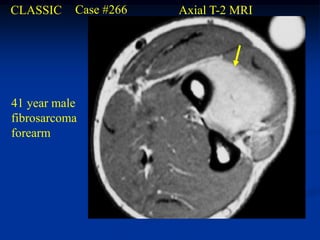

CLASSIC    Case #266   Axial T-2 MRI

41 year male

fibrosarcoma

forearm

Coronal T-2 MRI

Axial T-2 MRI